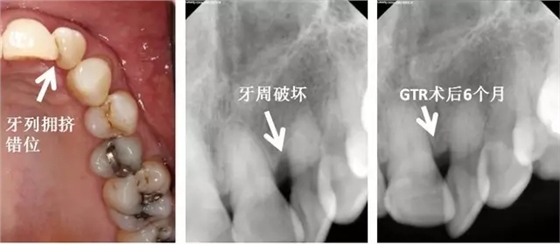

牙列因素

1. 牙列擁擠

2. 牙列不整齊

3. 咬合錯位

左上側(cè)切牙扭轉(zhuǎn),牙列擁擠,造成口腔衛(wèi)生困難,牙周破壞。告知患者牙列擁擠應(yīng)該予以治療以去除危險因子,再進(jìn)行牙周手術(shù)?;颊卟辉敢庹委煟x擇直接牙周手術(shù)。告知患者需要高質(zhì)量口腔衛(wèi)生,并且需要更為頻繁的專業(yè)清潔。